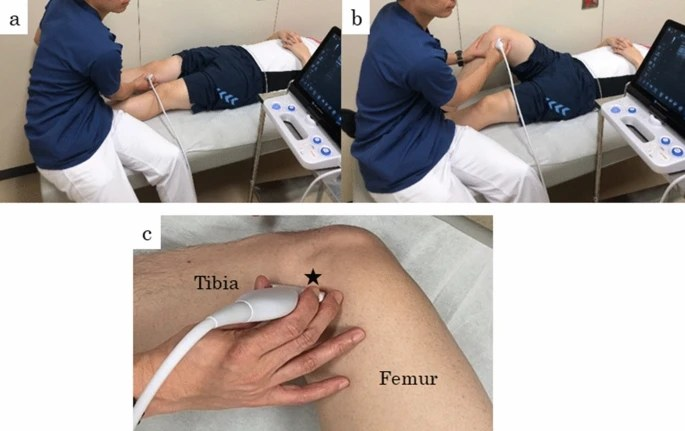

1/Có vết rách là sự hiện diện của vùng giảm âm trong chính sụn khớp liên quan tới mặt khớp , lưu ý ảnh giả hay sót chỗ đứt khe khoeo bằng cách so sánh với đầu gối bên không có triệu chứng

2/ Phương pháp thứ hai là quan sát chuyển động ra ngoài (đẩy ra) của sụn chêm khi kiểm tra động gối